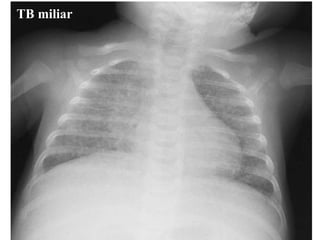

Rx tórax Niño: primoinfección. Patrón muy variable Adenopatías  hiliares ó mediastínicas: muy llamativas vs infiltrado Hiperinsuflación segmentaria y/o atelectasia (enfisema obstructivo <2 años)  Consolidación alveolar ó intersticial Derrame pleural  TBC miliar Adolescente: reactivación Cavitación Derrame pleural

TB miliar

Rx tórax Niño:primoinfección. Patrón muy variable Adenopatías hiliares ó mediastínicas: muy llamativas vs infiltrado Hiperinsuflación segmentaria y/o atelectasia (enfisema obstructivo <2 años) Consolidación alveolar ó intersticial Derrame pleural TBC miliar Adolescente: reactivación Cavitación Derrame pleural